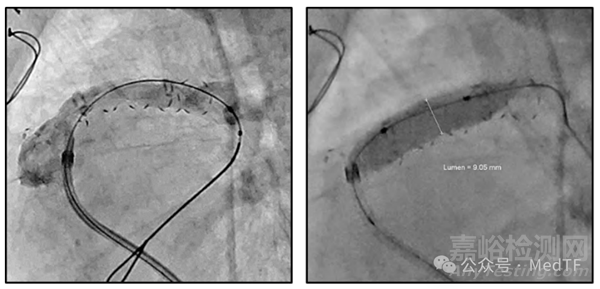

一個(gè)5個(gè)月大嬰兒植入直徑6mm的exGraft,之后通過介入手術(shù)將血管擴(kuò)大到9mm。(目前FDA批準(zhǔn)exGraft可以擴(kuò)大到原尺寸1.2倍,CE批準(zhǔn)可以擴(kuò)大到原尺寸1.4倍)

exGraft是一種采用PECA Labs專有ePTFE聚合物制備的人工血管。其術(shù)后可以通過球囊擴(kuò)張來增加人工血管直徑,從而使人工血管與兒童患者的生長(zhǎng)相匹配,同時(shí)還有助于避免成人再狹窄(變窄)。另外在術(shù)前,exGraft可擴(kuò)張的特性有助于解決獨(dú)特的解剖結(jié)構(gòu)。exGraft能夠在導(dǎo)管室進(jìn)行球囊擴(kuò)張,這為心臟護(hù)理團(tuán)隊(duì)治療患者提供了更大的靈活性。

exGraft除了可以擴(kuò)張這個(gè)特性外,還是唯一一款具有顯影功能的人工血管。exGraft之所以可顯影,是因?yàn)閑xGraft外表面帶有不透射線的油墨標(biāo)識(shí)。顯影功能使醫(yī)生能夠更容易識(shí)別血管位置、尺寸變化、血管內(nèi)部增生情況、扭轉(zhuǎn)、血管通暢等。